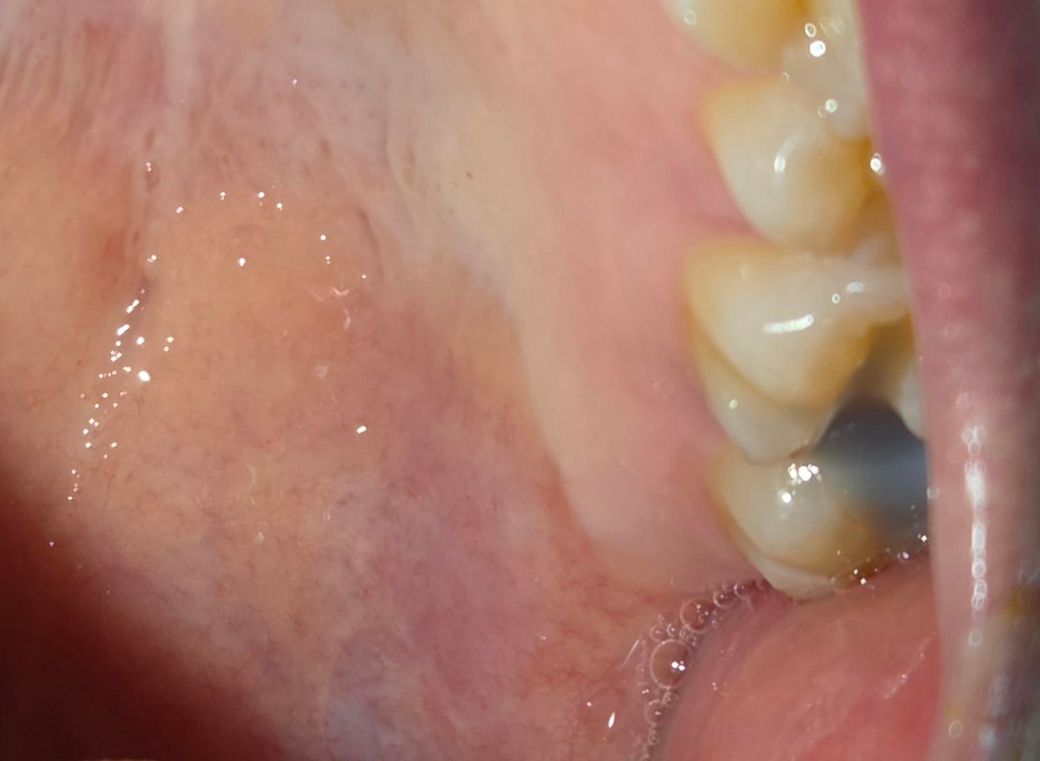

안녕하세요. 충치가 생겨 치과에서 인레이 치료를 받고왔는데 본만 뜨고 치아 갈아놓은 부분은 임시로 떼워주신다고 하셨습니다. 근데 대구치 6번 7번 둘 다 갈아버린 상황인데 떼워놓은건 7번만 해놓은거 같은데 6번은 왜 안해주신건지? 음식을 씹을 때 시린 상황입니다. 사진도 첨부드립니다.

• 1번 째 사진

사진상으론 6번,7번 같이 인레이를 위한 치아 형성한 상태로 보이고 6번도 임시충전재로 메꿔두었는데 떨어진 것이 아닌가 싶습니다. 치과가서 처치받으시면 됩니다.